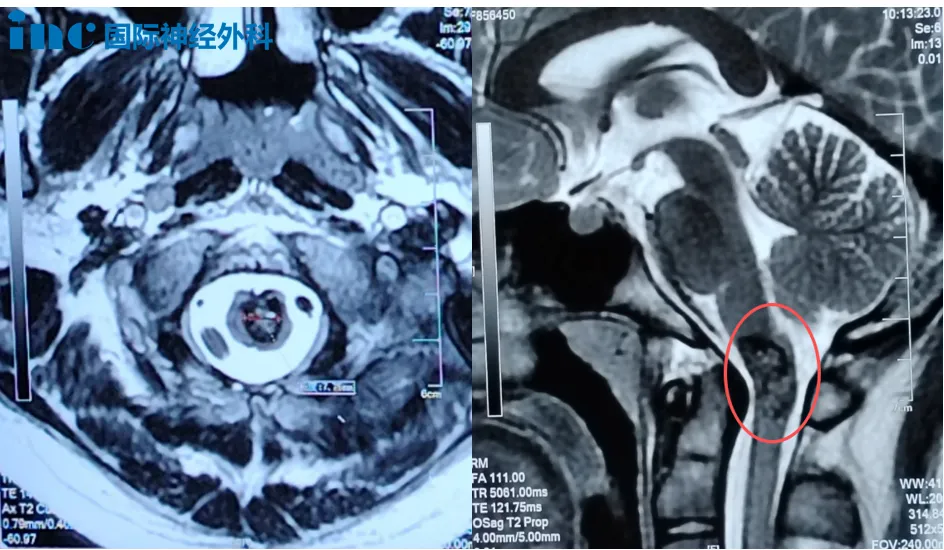

病例三:14岁男性延髓海绵状血管瘤

"延髓手术后是否需要气管切开?会出现瘫痪吗?"面对面咨询时巴特朗菲教授如何回应?

14岁男性患者小宇,今年8月突发头痛、呕吐症状,伴手脚阵发性麻木。头颅MRI检查提示延髓异常信号,考虑海绵状血管瘤。这个临床相对少见的病变,位于延髓与颈髓交界的生命中枢关键位置。住院治疗十天后,患者症状好转。至9月,所有不适症状消失,但复查MRI仍提示:延颈交界处异常信号,直径约8mm。症状虽消失,但病灶仍然存在。

在见巴特朗菲教授前,小宇父母最常听到的说法是:"这类手术后,孩子可能需要坐轮椅,可能出现瘫痪"。延髓位于脑干下部,连接桥脑与颈髓,富含多个神经核团,包括支配人体呼吸中枢的神经核团。因此,除运动功能受损的风险外,许多延髓手术患者还面临术后可能依赖气管插管的现实。

面对这个家庭的担忧,巴特朗菲教授的回应明确且坚定:手术有把握,且建议手术。虽然患儿目前无症状,但病灶位置危险,尺寸也已不小。"可以选择等待,但等待意味着承担随时可能出血的风险。"